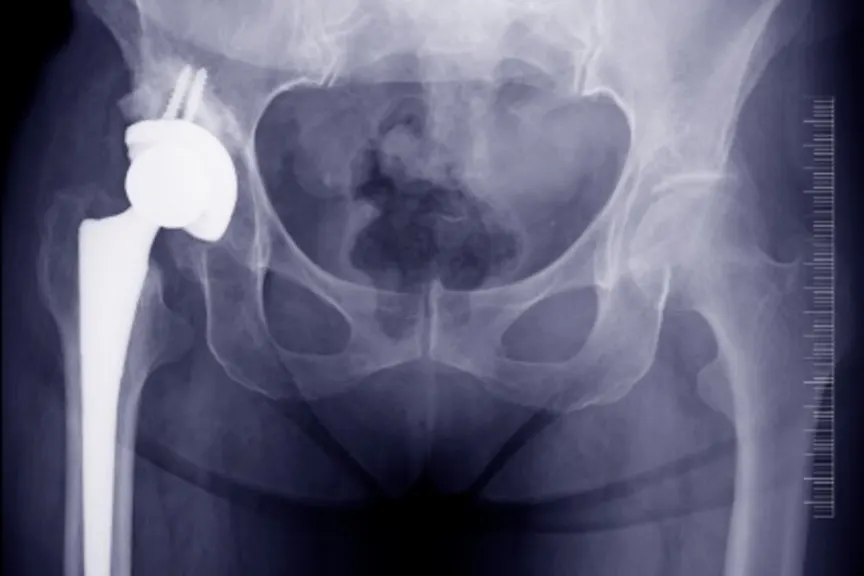

髋部骨折最常见的外科手术是一个髋关节置换术。通过用人工钛关节替换股骨的球和插座来实现该过程。